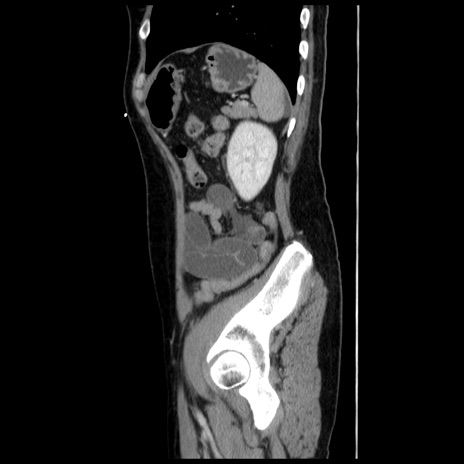

症例10(矢状断像)

【症例】 50歳代女性

【主訴】 腹痛

【現病歴】前日生レバーを食べた。今朝に排便あり。 昼前に突然発症の腹痛を生じ、当院救急外来を受診した。

【既往歴】 子宮筋腫にてで子宮全摘後

【身体所見】 意識清明、腹部:平坦、軟、下腹部やや左を中心に圧痛・反跳痛あり、筋性防御あり

【データ】WBC 7800、CRP 0.07